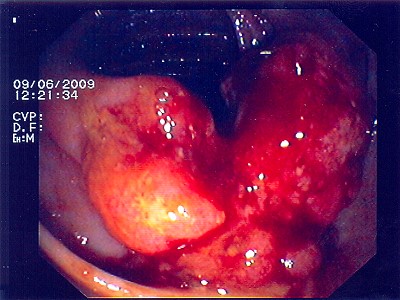

Abb. 4: Bei diesem bösartigen Gebilde handelt es sich um einen Krebstumor, der das Innere des Darmes nahezu vollständig verschlossen hat. Abb. 4: Bei diesem bösartigen Gebilde handelt es sich um einen Krebstumor, der das Innere des Darmes nahezu vollständig verschlossen hat.